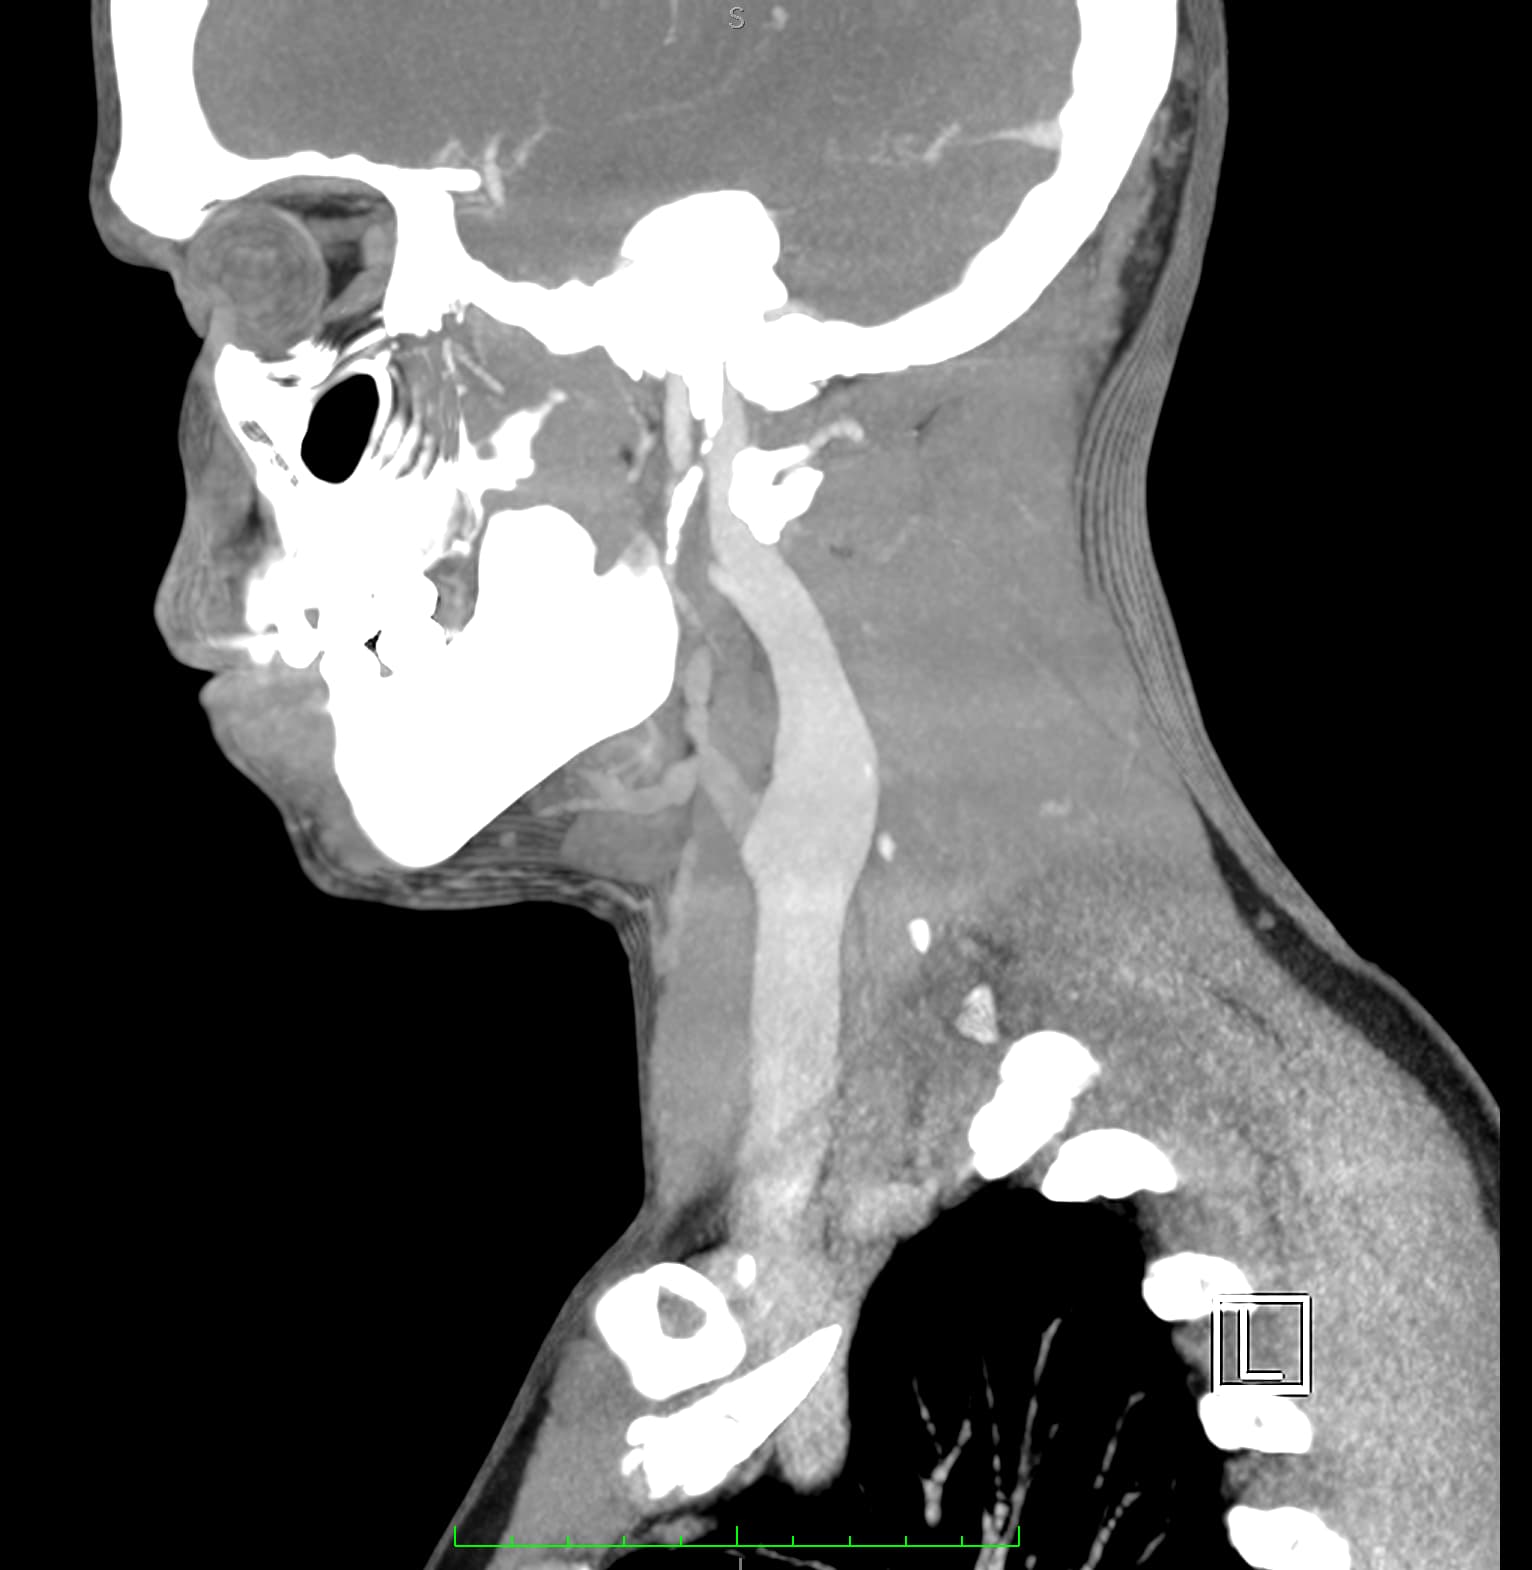

So, 2 years ago was the first time I came across Living with Eagle, filled with descriptions of all my symptoms, and a slew of scans showing very obvious bone chunks in the neck. Since I studied bio in college, and these bones are obvious, I figured I’d take a stab at looking at my own past scans and, low and behold, mild–but present–ossification of my stylohyoid ligament. Perhaps more relevant in my case, in the process of learning enough of the anatomy to understand axial images I noticed another weird thing–my right external carotid artery is in the wrong place. Instead of sitting lateral to my hyoid greater cornu, it’s medial. Hmm.

Tonsil surgery did solve the problem of my tonsils hurting, because they were gone, but no resolution of other symptoms. This was a year ago. I’ve been to PT, SLP, and now back to PT while I trial gabapentin for the neurologist. PT#2 discovered a bunch of significant atrophy in my upper right shoulder/back, and, you guessed it it’s all right sided. I’ve since then, thanks to radiopedia and Netter’s, also explored my images and noticed a few other anomalies in my scans, including an extended right thyroid superior cornu which appears to be pressing strongly into my neck also in the general area of pain, and an occipital artery branching off and wrapping around the internal carotid. Frustratingly these also weren’t mentioned on rads reports. My swallow study by the SLP showed obvious asymmetry with my swallow, but the SLP reported it symmetric and radiology apparently doesnt read the A/P view in their modified barium swallow studies? This is not inspiring faith in the academic institution I attended, but what can I possibly know they dont?

I’m here cause I’ve learned so much, and ya’ll seem to be the internet experts of weird head/neck issues adjacent to the stylohyoid chain. The docs keep seeing me, and keep ordering imaging, and seem to not be talking to each other at all? Frankly it seems to me the answers are in already in the images… so I’ve included several, perhaps you’ll see something helpful and can offer a suggestion… I just know I’m exhausted, frustrated, in so much pain all the time I cannot function which is so demoralizing, and it’s getting worse despite physician recommendations.

I wish I had better words for my existing doctors, or a doctor to visit familiar with these symptoms, if they’re sufficiently connected. Here are some scans for those interested, maybe someone has some ideas I can share with one of my doctors. I’m definitely at a loss and the pain constant and debilitating.